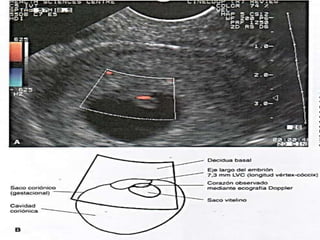

longitud vertex-coccix (LVC) se utiliza sobre todo

para lo embriones de mas edad.